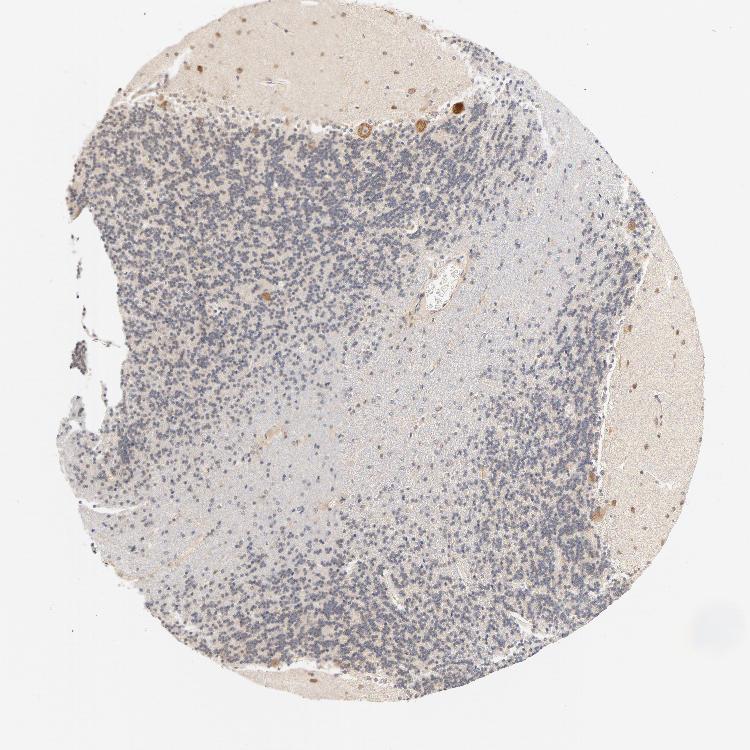

CEREBELLUM - Antibody stainingi

Antibody staining in the annotated cell types in the current human tissue is reported as not detected, low, medium, or high, based on conventional immunohistochemistry profiling in selected tissues. This score is based on the combination of the staining intensity and fraction of stained cells.

Each image is clickable and will lead to virtual microscopy that enables deeper exploration of all samples and also displays staining intensity scores, fraction scores and subcellular localization as well as patient and tissue information for each sample.

Antibody CAB004077Antibody CAB016316

Bergmann glia - cytoplasm/membrane Not detected-

Bergmann glia - nucleus Not detected-

GLUC cells - cytoplasm/membrane High-

GLUC cells - nucleus Not detected-

Purkinje cells -High

Purkinje cells - cytoplasm/membrane High-

Purkinje cells - dendrites Not detected-

Purkinje cells - nucleus Not detected-

Cells in granular layer -Medium

Cells in molecular layer -High

Granular cells - cytoplasm/membrane Not detected-

Granular cells - nucleus Not detected-

Molecular layer - neuropil Not detected-

Molecular layer cells - cytoplasm/membrane High-

Molecular layer cells - nucleus Not detected-

Processes in granular layer Not detected-

Processes in molecular layer Not detected-

Processes in white matter Not detected-

Synaptic glomeruli - capsule Not detected-

Synaptic glomeruli - core Low-

White matter cells - cytoplasm/membrane Not detected-

White matter cells - nucleus Not detected-